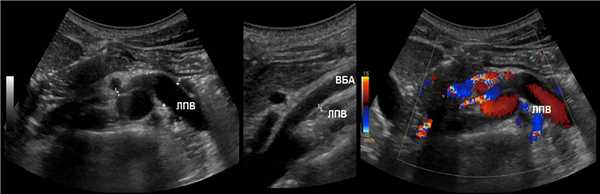

ППА проходит позади нижней полой вены. ЛПВ проходит через «пинцет» между аортой и верхней брыжеечной артерией. Иногда встречается кольцевидная ЛПВ, тогда одна ветвь располагается впереди, а другая — позади аорты.

Доплер почечных вен

Левая почечная вена проходит между аортой и верхней брыжеечной артерией. Аортомезентериальный «пинцет» может сдавливать вену, что ведет к венной почечной гипертензии. В положении стоя «пинцет» сжимается, а в положении лежа — раскрывается. При синдроме Щелкунчика затрудняется отток по левой яичковой вене. Это фактор риска развития левостороннего варикоцеле.

Из-за сдавления спектр ЛПВ похож на воротную вену — спектр выше базовой линии, постоянная низкая скорость, контур плавными волнами. Если соотношение диаметра ЛПВ перед и в зоне сужения более 5 или скорость потока менее 10 см/сек выносим заключение о повышении венозного давления в левой почке.

Задача. На УЗИ левая почечная вена расширена (13 мм), участок между аортой и верхней брыжеечной артерией заужен (1 мм). Кровоток в зоне стеноза с высокой скоростью (320 cм/сек), реверс кровотока в проксимальном сегменте. Заключение: Компрессия левой почечной вены аортомезентериальным «пинцетом» (синдром Щелкунчика).